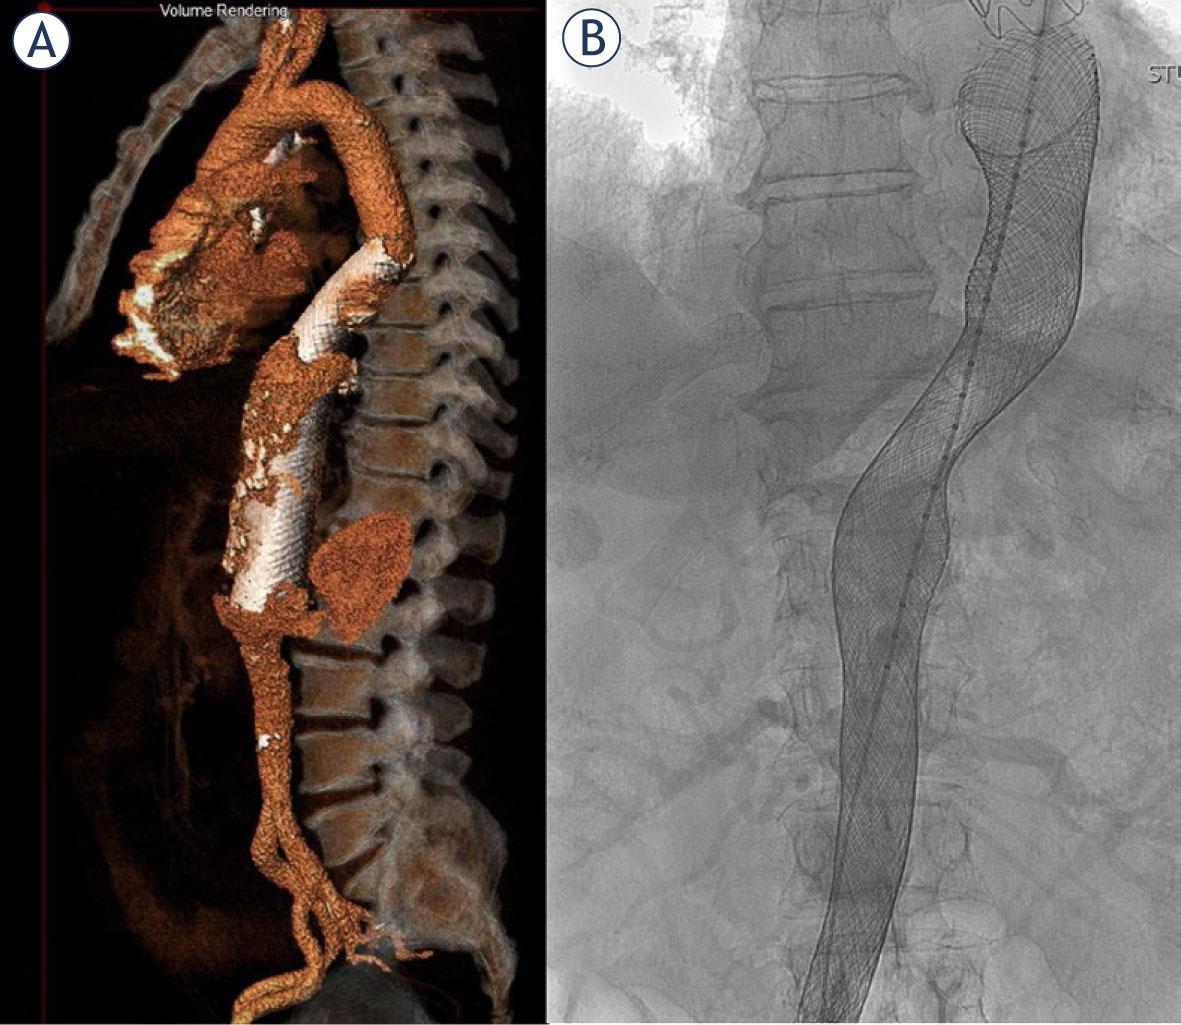

FIGURE 1.